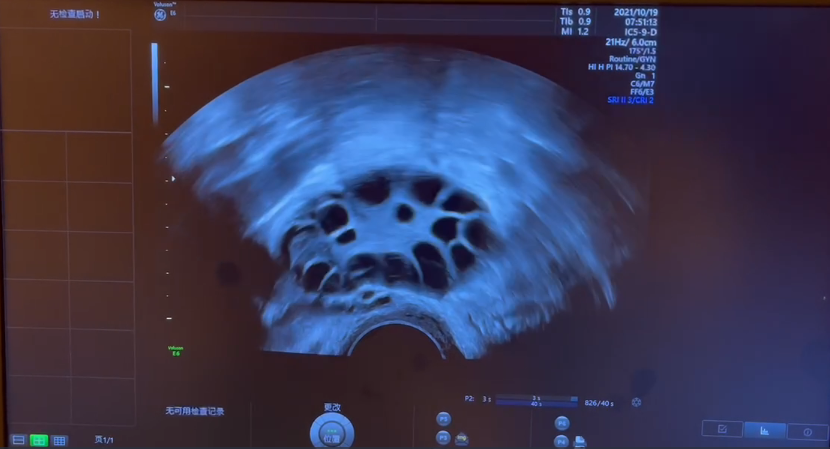

唐医生详细的了解了珍珍以往的病情之后给她做了进一步详细的检查,通过体格检查、内分泌激素、糖耐量试验、甲状腺功能、皮质醇等测定明确诊断其是典型的多囊卵巢综合征,同时伴有胰岛素抵抗,子宫输卵管造影发现双侧输卵管通畅,盆腔轻度粘连。